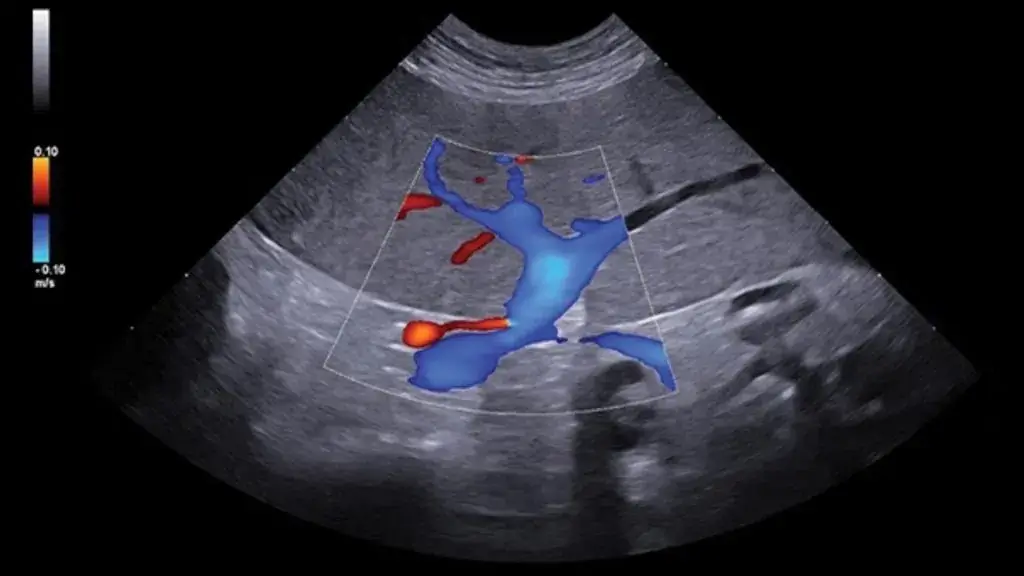

5) Basınç ve Volüm Yükü Değerlendirmesi

Kalbin sistolik ve diyastolik fonksiyonlarının incelenmesiyle; hastalığın ilerleyişi, yüklenme bulguları ve klinik riskin belirlenmesi

• Prognoz belirlemede kritiktir: Hastalığın seyri ve yaşam kalitesine etkisi hakkında güçlü öngörü sağlar.

• Takipte standarttır: Tedaviye yanıtın izlenmesi ve ilerleyişin kontrolünde vazgeçilmezdir.